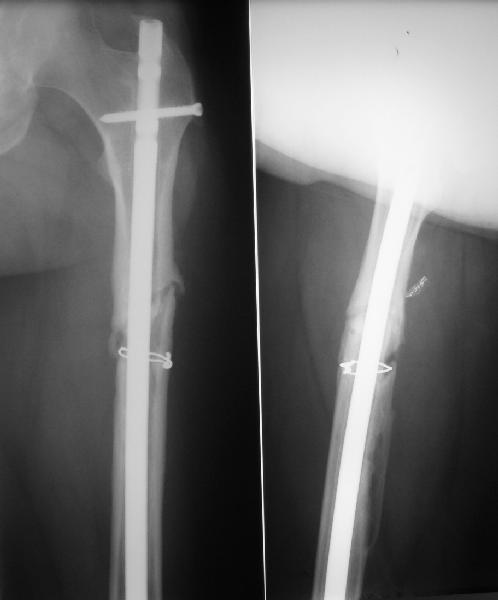

Пациент попал под наше наблюдение через 3 недели после первого остеосинтеза (фото 1). Учитывая, нестабильность остеосинтеза, выстоящий стержень закрыто перештифтовали (фото 2), через 3 месяца динамизация. К 5 месяцам имели укорочение 2 см, при том, что динамический винт стал статическим. От дальнейшей динамизации отказались, учитывая наличие контакта между фрагментами и возможность прогрессирования укорочения. К 1,5 года сращение не достигнуто (фото 3). Удалили гвоздь, выполнили дистракционный остеосинтез с целью стимуляции остеогенеза и компенсации укорочения (фото 4), потом закрыто перештифтовали после рассверливания (фото 5). На сегодняшний день, через 4 месяца после последней операции (фото 6) признаков регенерата нет, длина восстановлена, ходит без дополнительной опоры.